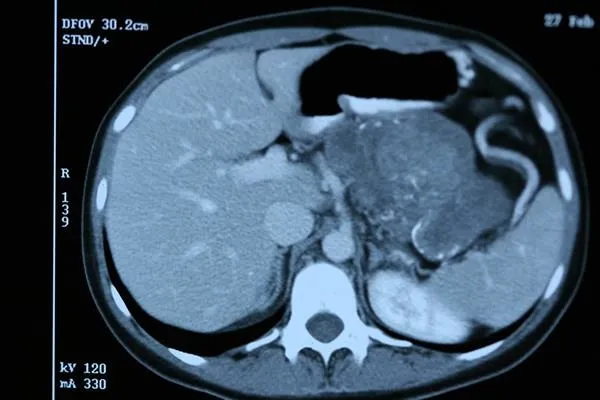

Hastalığın ilerlediği dönemlerinde şiddetli karın ve sırt ağrısı, sarılık, kilo kaybı, iştahsızlık, karında şişlik gibi bulgular ortaya çıkıyor. Tanı yöntemlerinde radyolojik yöntemler ve kan tahlillerinden faydalanılmaktadır.

Hastalar pankreasta kitle ile başvurduklarında, bu hastaların ameliyat olup olmayacakları ya da kemoterapi veya radyoterapiye aday olup olmayacakları endosonografi yöntemi ile teşhis edilebilmektedir.

Endosonografi, ucunda ultrason olan bir endoskoptur. Pankreas kanserinin tanı ve evrelemede yol gösterici bir yöntemdir. Bazı durumlarda oluşabilen komplikasyonların tedavisinde de kullanılmaktadır. Tanısal anlamda yapılan endosonografi sonrası hastalar aynı gün taburcu edilebilirler. Ancak hastalara endosonografi ile bir tümörün tanısı konulmuş ve hasta yönlendirilmiş olur.